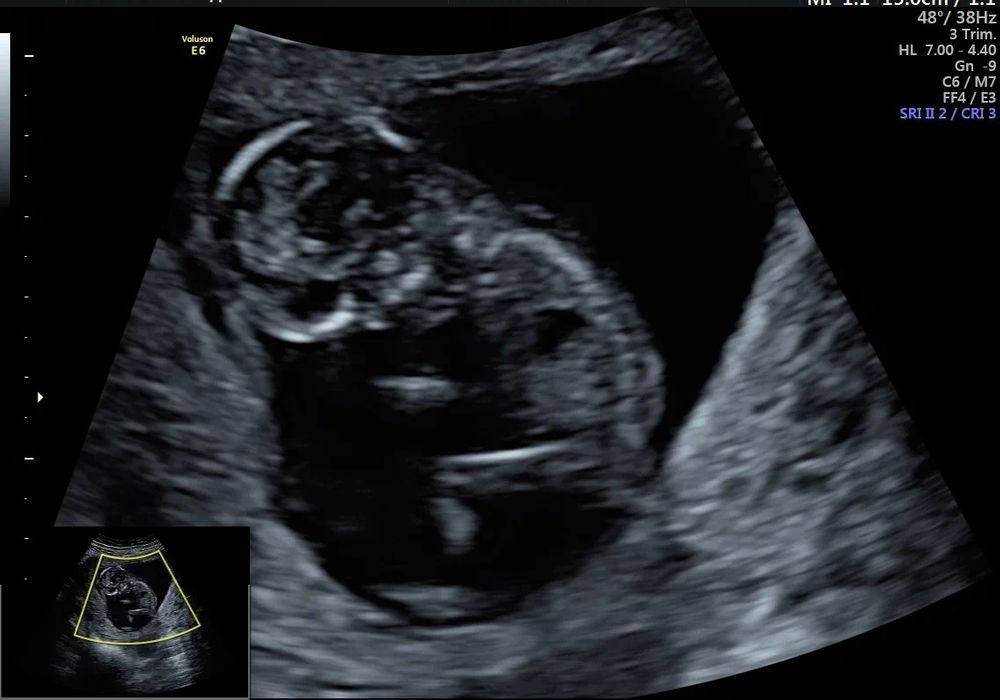

Наш первый скрининг 🥰

Боже, какая прелесть 😍😍😍 Настя, как я за вас рада ❤ растите, развивайтесь и рождайтесь здоровенькими 🙏🙏🙏

Сидит работает мужичок))) Здоровья Вам!